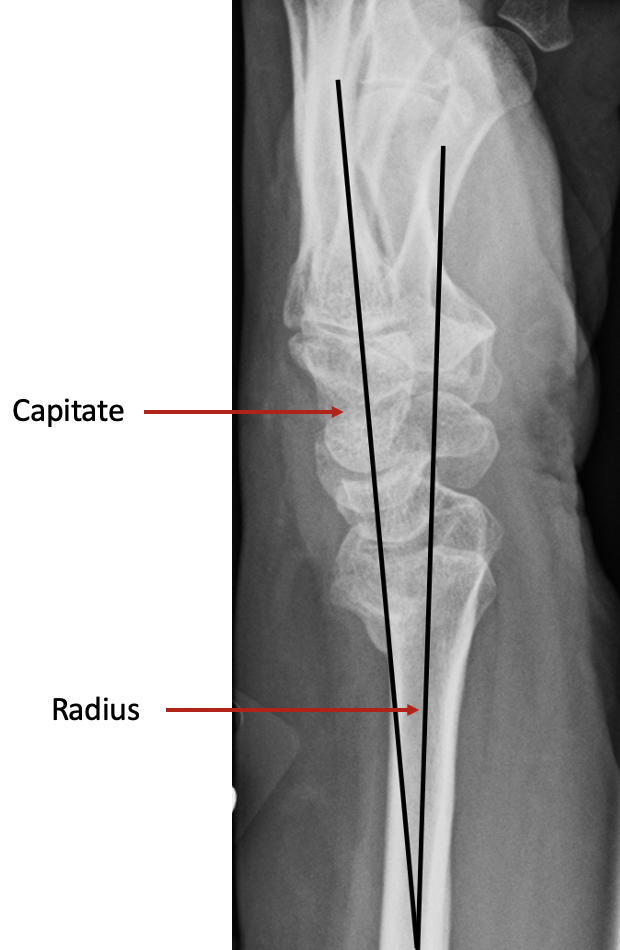

The surgery involves making an incision over the area of the malunion, and using a fine saw, the bone is divided. The bones are then repositioned in a more normal alignment and usually a small plate is used to fix the bone in its new position. On a normal side view xray (lateral view), if you draw a line up the middle of the radius bone, then this line should continue through the middle of the capitate bone. In a malunion, the continuing line does not pass through the middle of the capitate. The aim of surgery is primarily to restore this line.